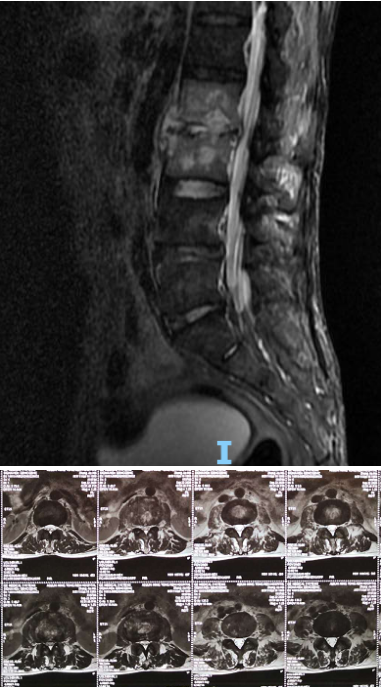

术前腰椎CT

术前腰椎MRI

患者出院后感腰部疼痛持续加重,到飞禽走兽攻略站 门诊就诊,以“腰椎感染”收住入院。患者发病后腰椎CT及MRI均提示腰2-3椎间隙变窄,椎板破坏,综合以上资料诊断”腰椎结核”。入院后经口服四联抗结核药物治疗3周,患者自觉腰部疼痛减轻,午后无发热及盗汗后,在全麻下行颈后路病灶清除、椎间植骨、椎弓根钉棒系统内固定术。手术顺利,术后继续抗结核治疗。患者恢复顺利,术后1周下床活动,无特殊不适。术后2周拆线、出院,院外继续口服抗结核药物治疗,定期门诊复查。